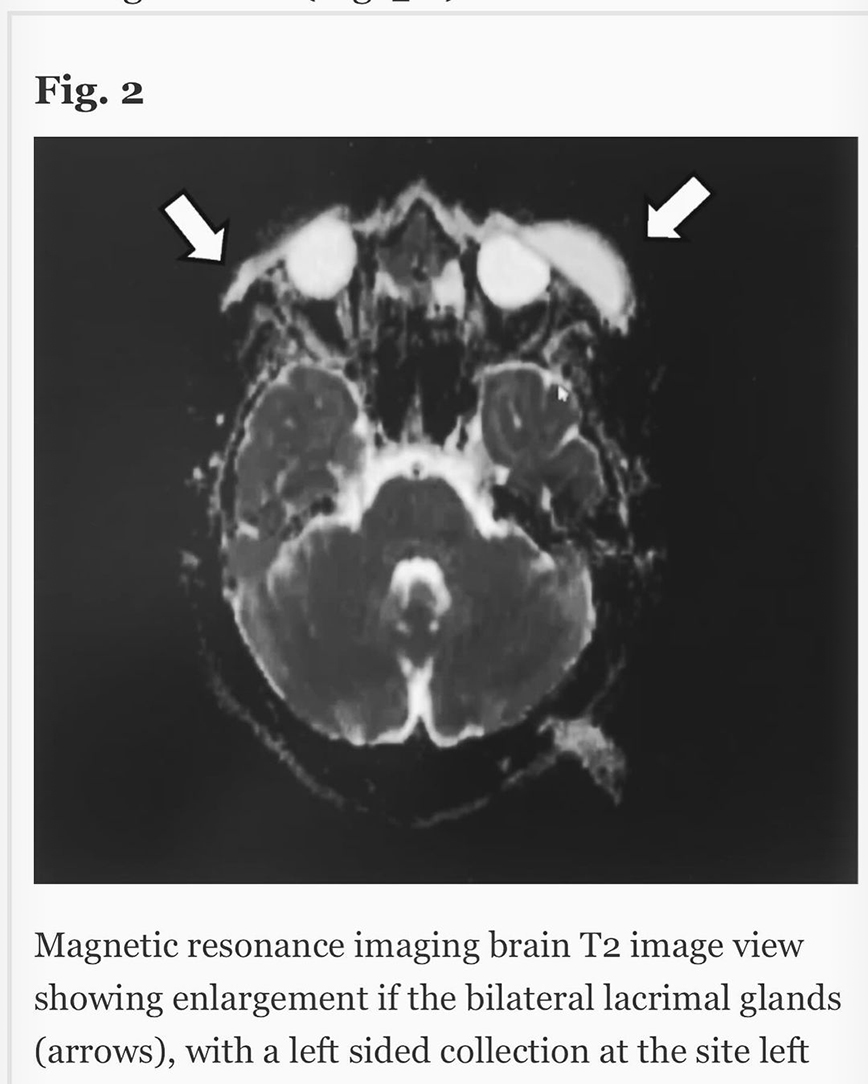

Ακούω κατά καιρούς διάφορες φήμες και έτυχε να ακούσω και τώρα κάποιες άλλες που δεν τιμούν οποίους τις διαδίδουν, οπότε θα ανεβάσω μερικές φωτογραφίες από τις δύο δύσκολες τελευταίες εβδομάδες. Ο πιο σημαντικός λόγος που τις ανεβάζω είναι όμως για να μοιραστώ την ιστορία μου για την αμφοτερόπλευρη δακρυοαδενίτιδα.

Αιτία ο κοβιντ ο άτιμος…Ψάξτε το. Μπορεί και κάποιος από εσάς να υποφέρει από αυτήν αυτό τον καιρό και να μην ξέρει πως να το διαχειριστεί.. Εγώ μπήκα στο νοσοκομείο και είχα την πιο απίστευτη γιατρό την Δήμητρα Π. να με προσέχει σε κάθε βήμα. Είμαι καλά τώρα όποτε πάμε γερά!», έγραψε στην ανάρτησή του ο Χρήστος Μάστορας.